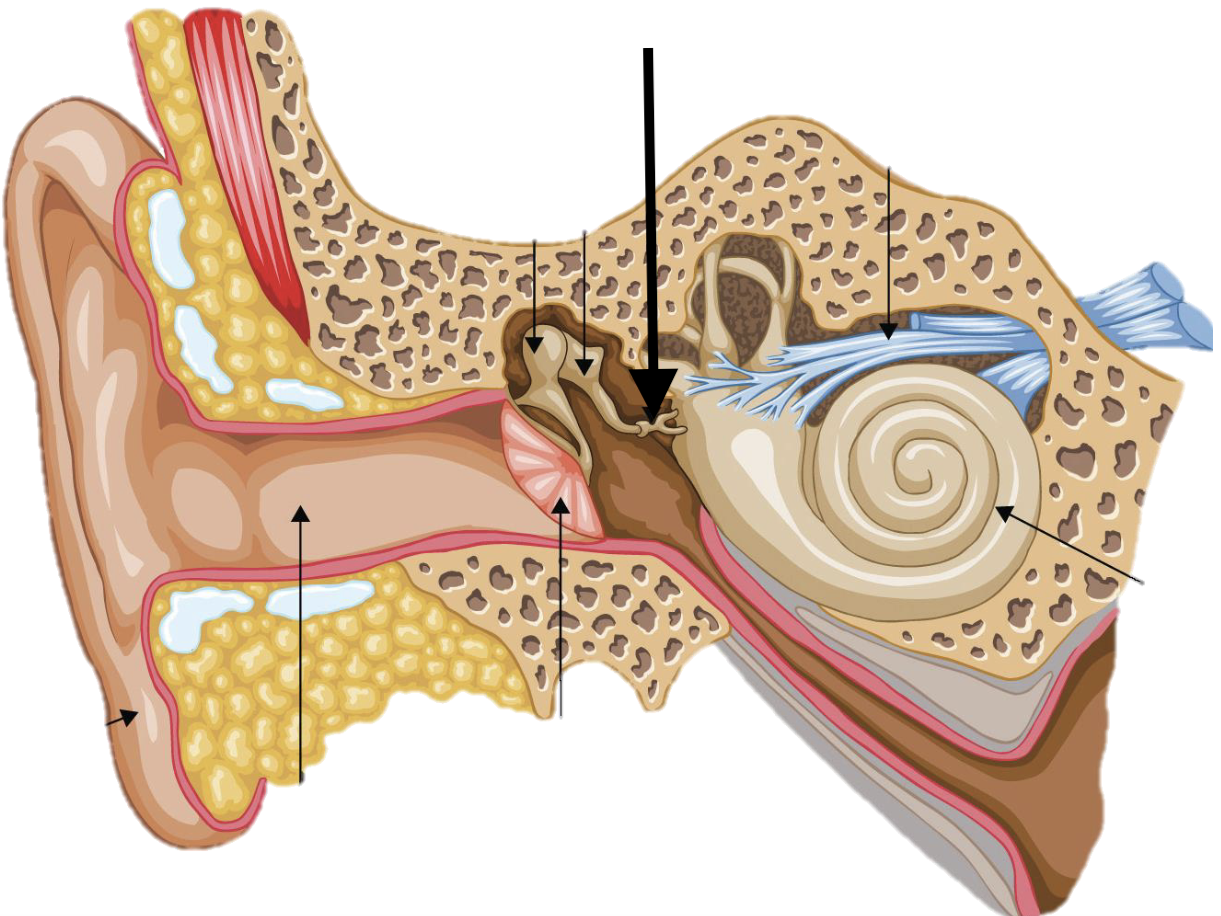

Name the feature of the ear ossicle

External acoustic meatus

Name the feature of the ear ossicle

Malleus

Name the feature of the ear ossicle

Incus

Name the feature of the ear ossicle

Stapes

Name the feature of the ear ossicle

Internal acoustic meatus

Name the feature of the ear ossicle

Cochlea

Name the feature of the ear ossicle

Temporal bone